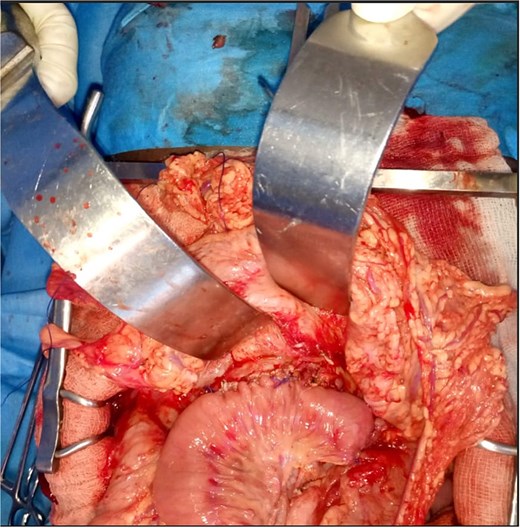

A 15-year-old girl was admitted with a painful epigastric mass associated with recurrent vomiting, evolving over two years. She reported repeated episodes of refractory abdominal pain and progressive weight loss, resulting in significant disruption of school attendance. There was no family history of pancreatic disease and no history of alcohol or drug use. Physical examination revealed a fixed, mildly tender epigastric mass measuring ~7 cm. Laboratory investigations showed microcytic hypochromic anemia (hemoglobin 7.2 g/dl) and a prothrombin rate of 78.9%. Renal function, serum electrolytes, fasting blood glucose, liver function tests, tumor markers (CA 19–9 and CEA), serum calcium, and triglyceride levels were within normal limits. Computed tomography revealed pancreatic macrocalcifications, marked dilation of the Wirsung duct, and a large pancreatic pseudocyst measuring 107 × 83 × 140 mm, with minimal intraperitoneal fluid (Fig. 1). These findings were consistent with CCP complicated by a pancreatic pseudocyst. After appropriate preoperative optimization, exploratory laparotomy was performed under general anesthesia. Intraoperative findings included a fibrotic, inflamed pancreas, a large interhepatogastric pseudocyst arising from the pancreatic body, and signs of segmental portal hypertension. Needle aspiration of the pancreatic parenchyma yielded a brown-colored pancreatic juice (Fig. 2). Longitudinal pancreatotomy centered on the dilated Wirsung duct revealed multiple intraductal calculi, which were extracted, followed by ductal irrigation (Fig. 2). A side-to-side pancreaticojejunostomy using a transmesocolic Roux-en-Y limb was performed (Fig. 3). Cholecystectomy, side-to-side choledochoduodenostomy, and cystogastrostomy with cavity drainage were also carried out. The postoperative course was uneventful. Oral feeding was started on postoperative day 5. Histopathological examination confirmed chronic pancreatitis with pancreatic pseudocyst. Long-term follow-up demonstrated complete pain relief, weight gain, and resumption of normal school activities.

Intraoperative view demonstrating removal of intraductal pancreatic calculi (white arrow) after punction of dilated Wirsung duct and pancreatotomy.